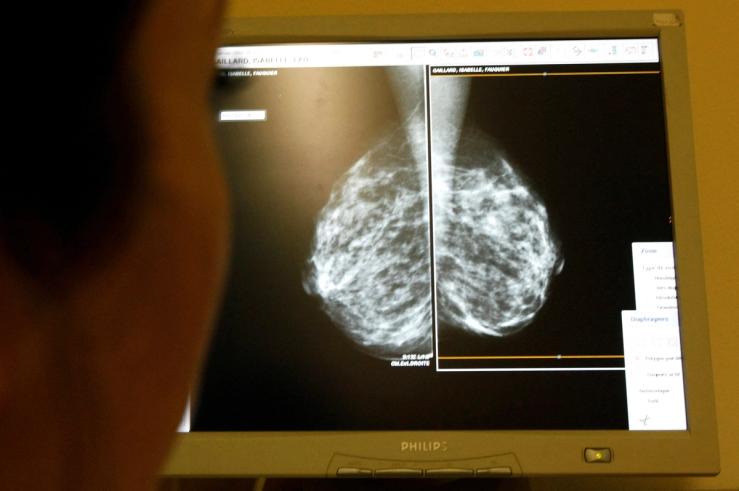

The CEO of NYC Health + Hospitals told a conference: “We could replace a great deal of radiologists with AI” if the regulatory environment permitted it, with major cost savings. AI is now “better than human beings” at spotting breast cancers, he said.